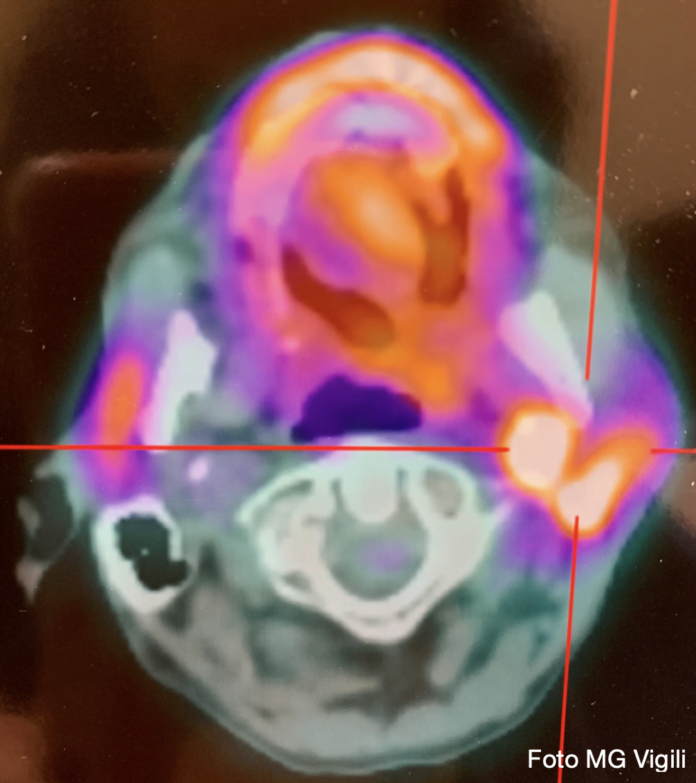

Ruolo della FDG PET/CT nello studio dei linfonodi latero cervicali metastatici dei tumori testa collo a primitività ignota. La presenza di metastasi linfonodali latero cervicali (CLNM) al momento della diagnosi è uno dei fattori prognostici sfavorevoli più rilevante nei pazienti con carcinoma squamoso della testa e del collo a primitività ignota (HNSCC).

Uno studio italiano dell’Università di Ferrara, ha analizzato l’utilizzo di 2-deoxy-2[18F]fluoro-D-glucose (FDG) PET/CT nello studio dei pazienti affetti d CLNM.

Sono stati retrospettivamente analizzati 65 pazienti (53 maschi, 12 femmine, età media 65.7 anni), sottoposti a FDG PET/CT per HNSCC trattati tra 2015-2020.

Tutti i Linfonodi sospetti avevano avuto una diagnosi di conferma citologica od istologica.

La captazione (SUVmax) dei pazienti fumatori aveva valori significativamente superiori rispetto a quella dei pazienti non fumatori (p = 0.04), così come il SUVmax dei pazienti p16 positivi rispetto a quelli p16 negativi (p = 0.089).

Il valore cut-off di SUVmax per la identificazione di CLNM era quantificato in 5.8 (AUC = 0.62, sensitività 71.4% e specificità 72.7%).